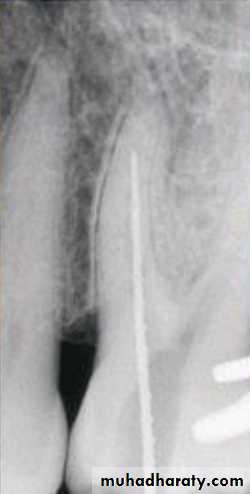

Standardized Technique

Standardized tech. Illustration